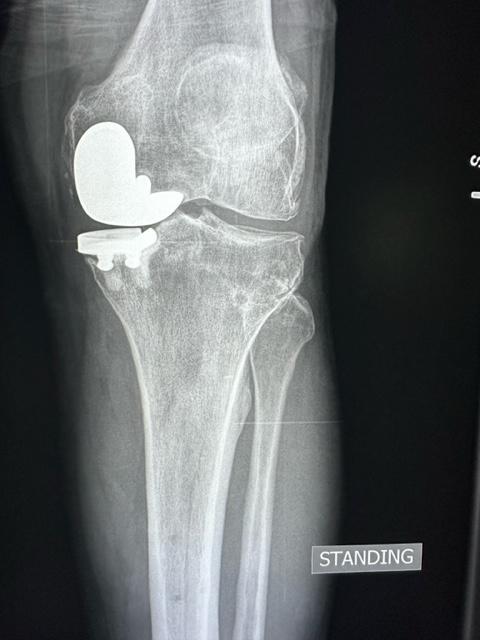

When I first opened it and looked at the T1 I thought I was looking at something aggressive like osteosarcoma.

But once I started looking through it I *think* it’s a prox tib fib capsule ganglion run wild…my impression is that it’s a ganglion with extensive osseuous retention at the fibular head and then it found it’s way into the extensor digitorum longus tendon at its tibial origin and decompressed all the way to the ankle. Distally it seems to break free of the tendon and cause some peroneal denervation change. I’ve seen peroneal perineural ganglia from the tib fib capsule but never this…so before I sign it as such I’d love to hear if anyone has other ideas!